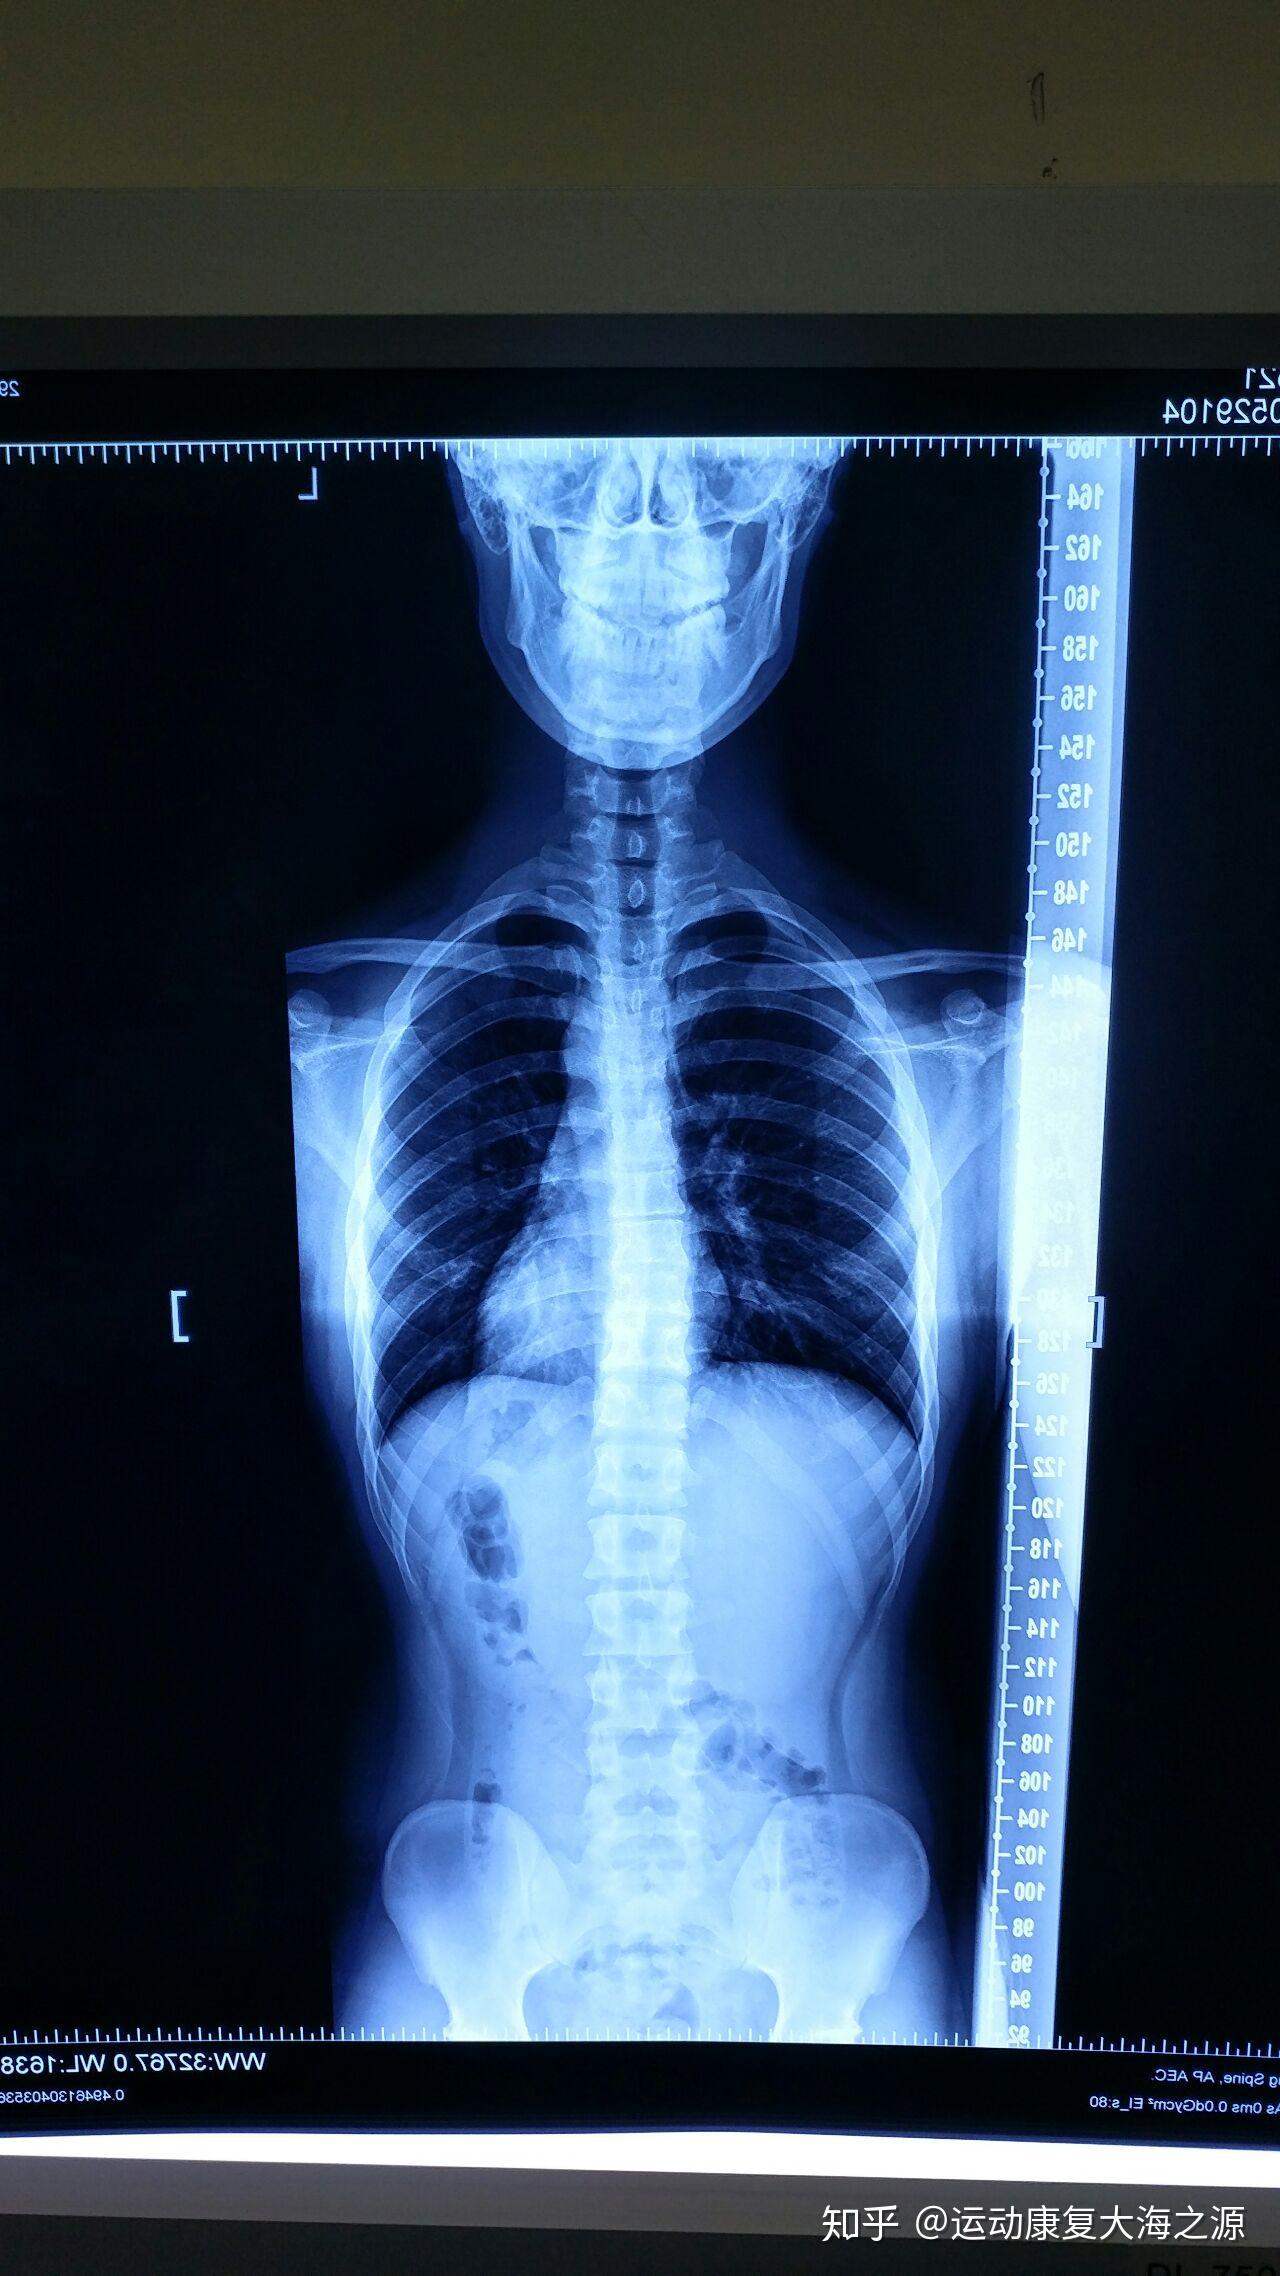

先天性脊柱侧凸站立位全脊柱正侧位:胸椎右侧弯,cobb角53°(t2-t7),t3